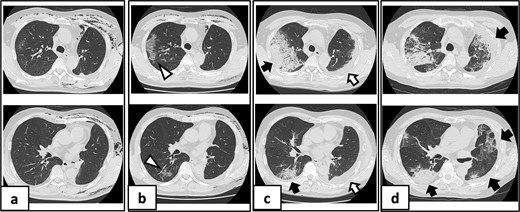

On POD 10, he developed fever and tested positive for COVID-19 by reverse transcription-polymerase chain reaction. Nosocomial transmission was suspected given recent ward cases during the delta variant outbreak. Chest computed tomography showed minimal peripheral ground-glass opacities in the right upper lobe (Fig. 2a and b). He received remdesivir (5 days) and dexamethasone (7 days), maintained adequate oxygenation without supplemental oxygen, and was discharged on POD 21 after clinical improvement.

Serial chest imaging demonstrating pulmonary complications. (a) Postoperative day (POD) 10: Initial presentation without significant abnormalities. (b) POD 16: Peripheral ground-glass opacities (arrowheads). (c) POD 27: Patchy consolidation (solid arrows) with new ground-glass opacities and pleural effusion (open arrows). (d) POD 36: Progressive consolidation (solid arrows).

On POD 27, he was readmitted with fever (38.2°C) and respiratory failure. COVID-19 testing was negative. Chest computed tomography revealed patchy consolidations mixed with ground-glass opacities in the right upper lobe with notable expansion, and new ground-glass opacities in the right middle lobe and residual left upper lobe periphery (Fig. 2c). Findings excluded recurrent air leak or aspiration pneumonia. Despite antibiotic therapy, oxygen requirements increased to 2 L by POD 29.

Methylprednisolone pulse therapy (1 g/day for 3 days) was initially administered, followed by oral prednisolone (30 mg). However, oxygen requirements increased to 4 L on POD 31 (Fig. 3). On POD 36, a second methylprednisolone pulse course was initiated with cyclosporine A (150 mg) owing to progressive consolidation on chest imaging (Fig. 2d). Oxygen support was discontinued by POD 38, and he was discharged on POD 52. Follow-up image on POD 104 showed substantial radiological improvement (Fig. 4). Immunosuppressive medications were successfully tapered and discontinued by POD 329. This case was diagnosed as delayed-onset OP as a manifestation of post-acute COVID-19 syndrome, characterized by the biphasic clinical course and distinctive radiological progression occurring weeks after acute COVID-19 infection.